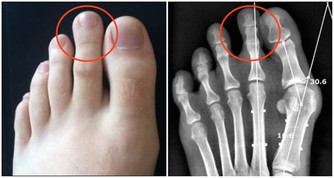

在我的從醫經歷中,我發現眾多病人的病根竟然是主食吃得太少。

多少次,我問病人,你主食吃得多嗎?他們回答,“很多啊”,“還可以”。然而細細追問下,你才會知道,很多身材高大的人,那所謂的“很多”就是早餐5毛錢的包子、晚餐1兩不到的麵條。